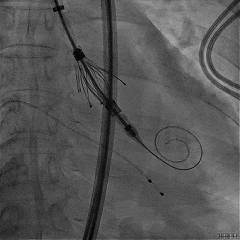

房间隔穿刺高度4.1cm

SGC穿房间隔进入左房

第一枚XTR进入左房

在1区进行轨迹测试和Orientation调整

将调整好的夹子移动至3区下左室

在左室打开夹子确认Orientation